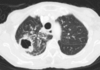

80

Patrón en panal

Patrón intersticial bibasal

82